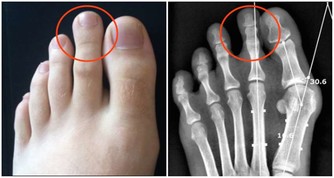

婆婆和先生懷疑的眼光,讓她幾乎崩潰。醫生仔細詢問,她才回憶起自己結婚前,曾在路邊小攤上打過耳洞。“很可能就是那次埋下禍根。”

醫生提醒,梅毒、艾滋病等並不僅僅通過性傳播,紋身、打耳洞等有創美容,如果器具消毒不到位,也都可能傳播病毒。